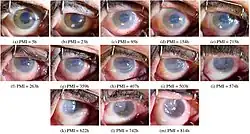

Secondary changes in corneal opacity

Secondary changes may be seen in long-standing cases include: hyaline degeneration, calcareous degeneration, pigmentation and atheromatous ulceration.[4]